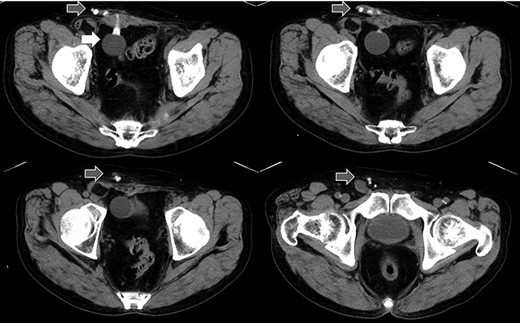

A 75-year-old male was referred for the treatment of a right IH. He also had received AUS implantation for a similar medical course. Abdominal CT demonstrated that a balloon was located beside the bladder and that the connecting catheter went through the rectus abdominis muscle and reached to the right scrotum through the subcutaneous layer (Fig. 5). The catheter was palpable subcutaneously; therefore, skin incision was placed on the outer site rather than in the normal situation. The diagnosis was indirect hernia and we did not observe any components of the AUS in the inguinal canal and repaired it using the Lichtenstein method.

Abdominal CT in Case 2: the balloon was located near the bladder and the tube went through rectus abdominis muscle; balloon, white arrow; tubes, gray arrows.

There is a report that contraindicates the laparoscopic repair for IH because of scaring and adhesion after RP in the preperitoneal space [4]. In addition, it is difficult to avoid damage to the AUS device without tactile perception. Therefore, we chose an anterior approach, which is the most familiar method for us. The operation of Case 1 patient was difficult because of adhesion in the inguinal canal, but Case 2 was not. The difference between the two cases was whether the catheter went through inguinal canal or not. We could detect the tract of the catheter by preoperative CT and US, which could be a good predictor for adhesion or difficulty in the operation.